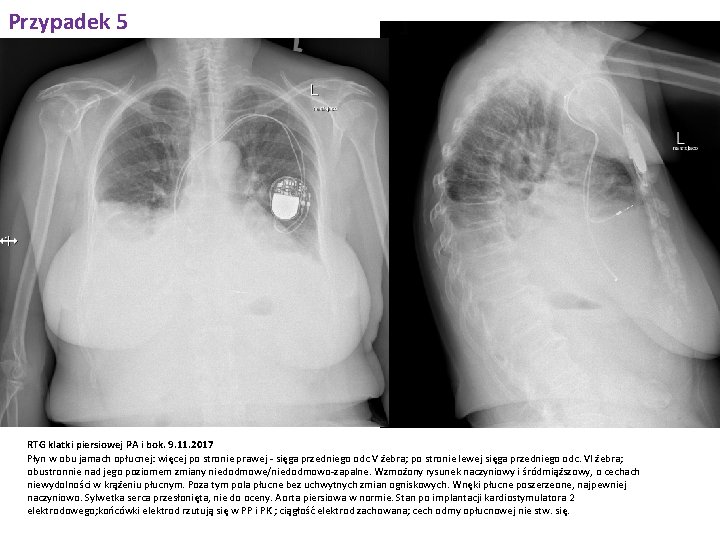

Przypadek 5 RTG klatki piersiowej PA i bok. 9. 11. 2017 Płyn w obu jamach opłucnej: więcej po stronie prawej - sięga przedniego odc V żebra; po stronie lewej sięga przedniego odc. VI żebra; obustronnie nad jego poziomem zmiany niedodmowe/niedodmowo-zapalne. Wzmożony rysunek naczyniowy i śródmiąższowy, o cechach niewydolności w krążeniu płucnym. Poza tym pola płucne bez uchwytnych zmian ogniskowych. Wnęki płucne poszerzeone, najpewniej naczyniowo. Sylwetka serca przesłonięta, nie do oceny. Aorta piersiowa w normie. Stan po implantacji kardiostymulatora 2 elektrodowego; końcówki elektrod rzutują się w PP i PK ; ciągłość elektrod zachowana; cech odmy opłucnowej nie stw. się.

Przypadek 5 RTG klatki piersiowej PA i bok. 13. 11. 2017 Stan po nakłuciu prawej jamy opłucnej - cech odmy opłucnowej nie stw. się. W por. do bad. poprz. z dn. 09. 11. 2017 r - regresja ilości płynu w prawej jamie opłucnej - aktualnie sięga przedniego odc. żebra VI; po stronie lewej płyn spłycający kąt p-ż; obustronnie, nad poziomem płynu zmiany niedodmowe/niedodmowo-zapalne. Drobne zmiany guzkowo-włókniste w szczycie lewego płuca. Poza tym pola płucne bez zmian ogniskowych, o cechach niewydolności w krążeniu płucnym. Wnęki płucne poszerzeone, najpewniej naczyniowo. Ocena sylwetki serca utrudniona - wydaje się być powiększona. Aorta piersiowa w normie. Zmiany zwyr. kręgosłupa Th. Stan po implantacji kardiostymulatora 2 elektrodowego; końcówki elektrod rzutują się w PP i PK ; ciągłość elektrod zachowana;

Przypadek 5 „Porcelanowy” 17. 11. 2017 Dwufazowe badanie TK klatki piersiowej. Płyn w jamach opłucnych gr. do L - 30 mm, P - 53 mm; powyżej płynu pasmowate obszary zagęszczeń miąższu o charakterze zmian niedodmowych segm 10 oraz przywnękowo w segm. 9 PP. Poza tym płuca bez zmian ogniskowych. Guzkowo-włókniste zmiany w szczytach obu płuc. Podopłucnowo w segm. 4 PP guzek śr. 6 mm- zmiana niecharakterystyczna. W okienku aortalno-płucnym pojedynczy powiększony węzeł chłonny o wym. 13 x 19 x 14 mm. Poza tym śródpiersie bez adenopatii. Serce powiększone, dwukomorowe. Stan po implantacji stymulatora serca dwujamowego. Duża naczynia klatki piersiowej w normie. Zmiany zwyrodnieniowo-wytwórcze odc. Th kręgosłupa. Proponuje kontrole po ewakuacji płynu z jam opłucnych. W lewym płacie tarczycy hypodensyjne zmiany ogniskowe z obecnością zwapnień - do oceny w badaniu USG. Nadnercza niepowiększone, bez zmian ogniskowych. Inkrustowana solami wapniowymi ściana pęcherzyka żółciowego - pęcherzyk porcelanowy - do dalszej diagnostyki.

Przypadek 5 „Porcelanowy” 20. 11. 2017 CT jamy brzusznej oraz miednicy. W badaniu zwraca uwagę pęcherzyk żółciowy, którego ściany są inkrustowane wapniem - pęcherzyk porcelanowy; przylegający miąższ wątroby, w otoczeniu loży pęcherzyka prawdopodobnie z cechami nacieku grubości do 7 mm; ponadto widocznie nieznacznie poszerzone gałęzie sektorowe przewodów żółciowych wewnątrzwątrobowych powyżej loży pęcherzyka żółciowego (w segm. 5) oraz zaburzenia perfuzji miąższu wątroby w sąsiedztwie - całość obrazu sugeruje obecność procesu npl w obrębie pęcherzyka żółciowego. Poza tym wątroba niepowiększona, bez zmian ogniskowych. W świetle pęcherzyka żółciowego widoczne uwapnione złogi. PZW poszerzony na całej długości do 14 mm; poszerzone przewody wątrobowe wspólne, prawy do 9 mm, lewy do 5 mm. Trzustka niepowiększona, bez zmian ogniskowych. Przewód trzustkowy nieposzerzony. Obie nerki w położeniu typowym bez zmian ogniskowych, UKM- y bez zastoju. Nadnercza typowego kształtu, wielkości, bez zmian ogniskowych. Śledziona niepowiększona. Naczynia duże jamy brzusznej w normie. Powiększonych węzłów chłonnych nie stw się. Płyn w jamach opłucnych gr. do L - 20 mm, P - 35 mm; powyżej płynu pasmowate obszary zagęszczeń miąższu o charakterze zmian niedodmowych. Struktury kostne objete badaniem bez zmian destrukcyjnych. W macicy endometrium pogrubiałe do 10 mm.